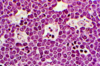

Describe the appearane of neutrophils.

Multilobed nuclei with lots of granules

Describe the appearance of eosinophils.

Bi-lobed nucleus with red granules